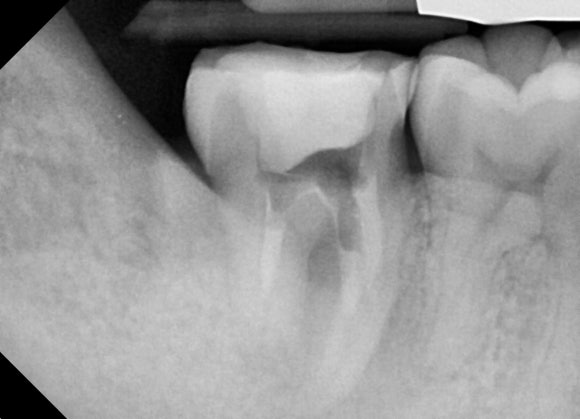

조금 더 확대해서 보겠습니다.

사랑니가 어금니를 밀고 있고,

어금니의 뿌리는 마치 부러진 것처럼 흡수되어 있습니다.

우리 몸의 단단한 조직 - 뼈나 치아-은

염증이 발생했을 때 스스로를 녹이거나

혹은 스스로를 덧붙이는 방식으로

대응합니다.

이 경우엔 녹이는 방향입니다.